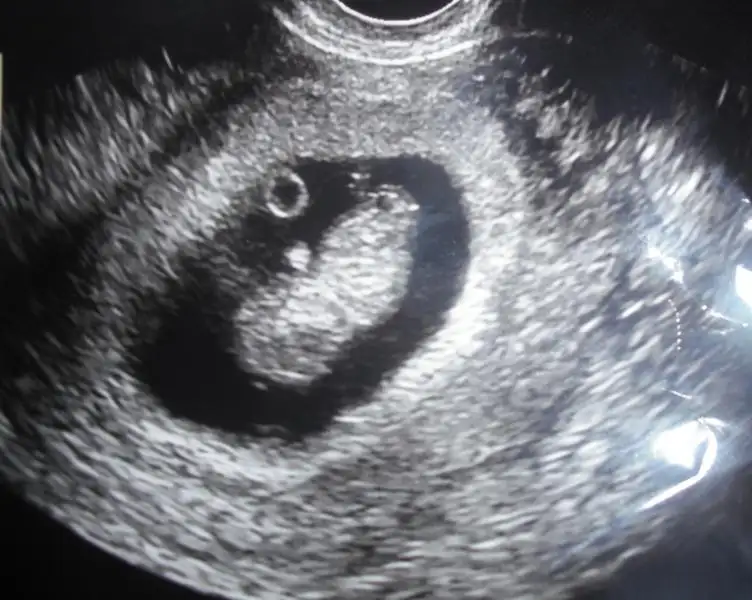

İşte bu da benim fındığım